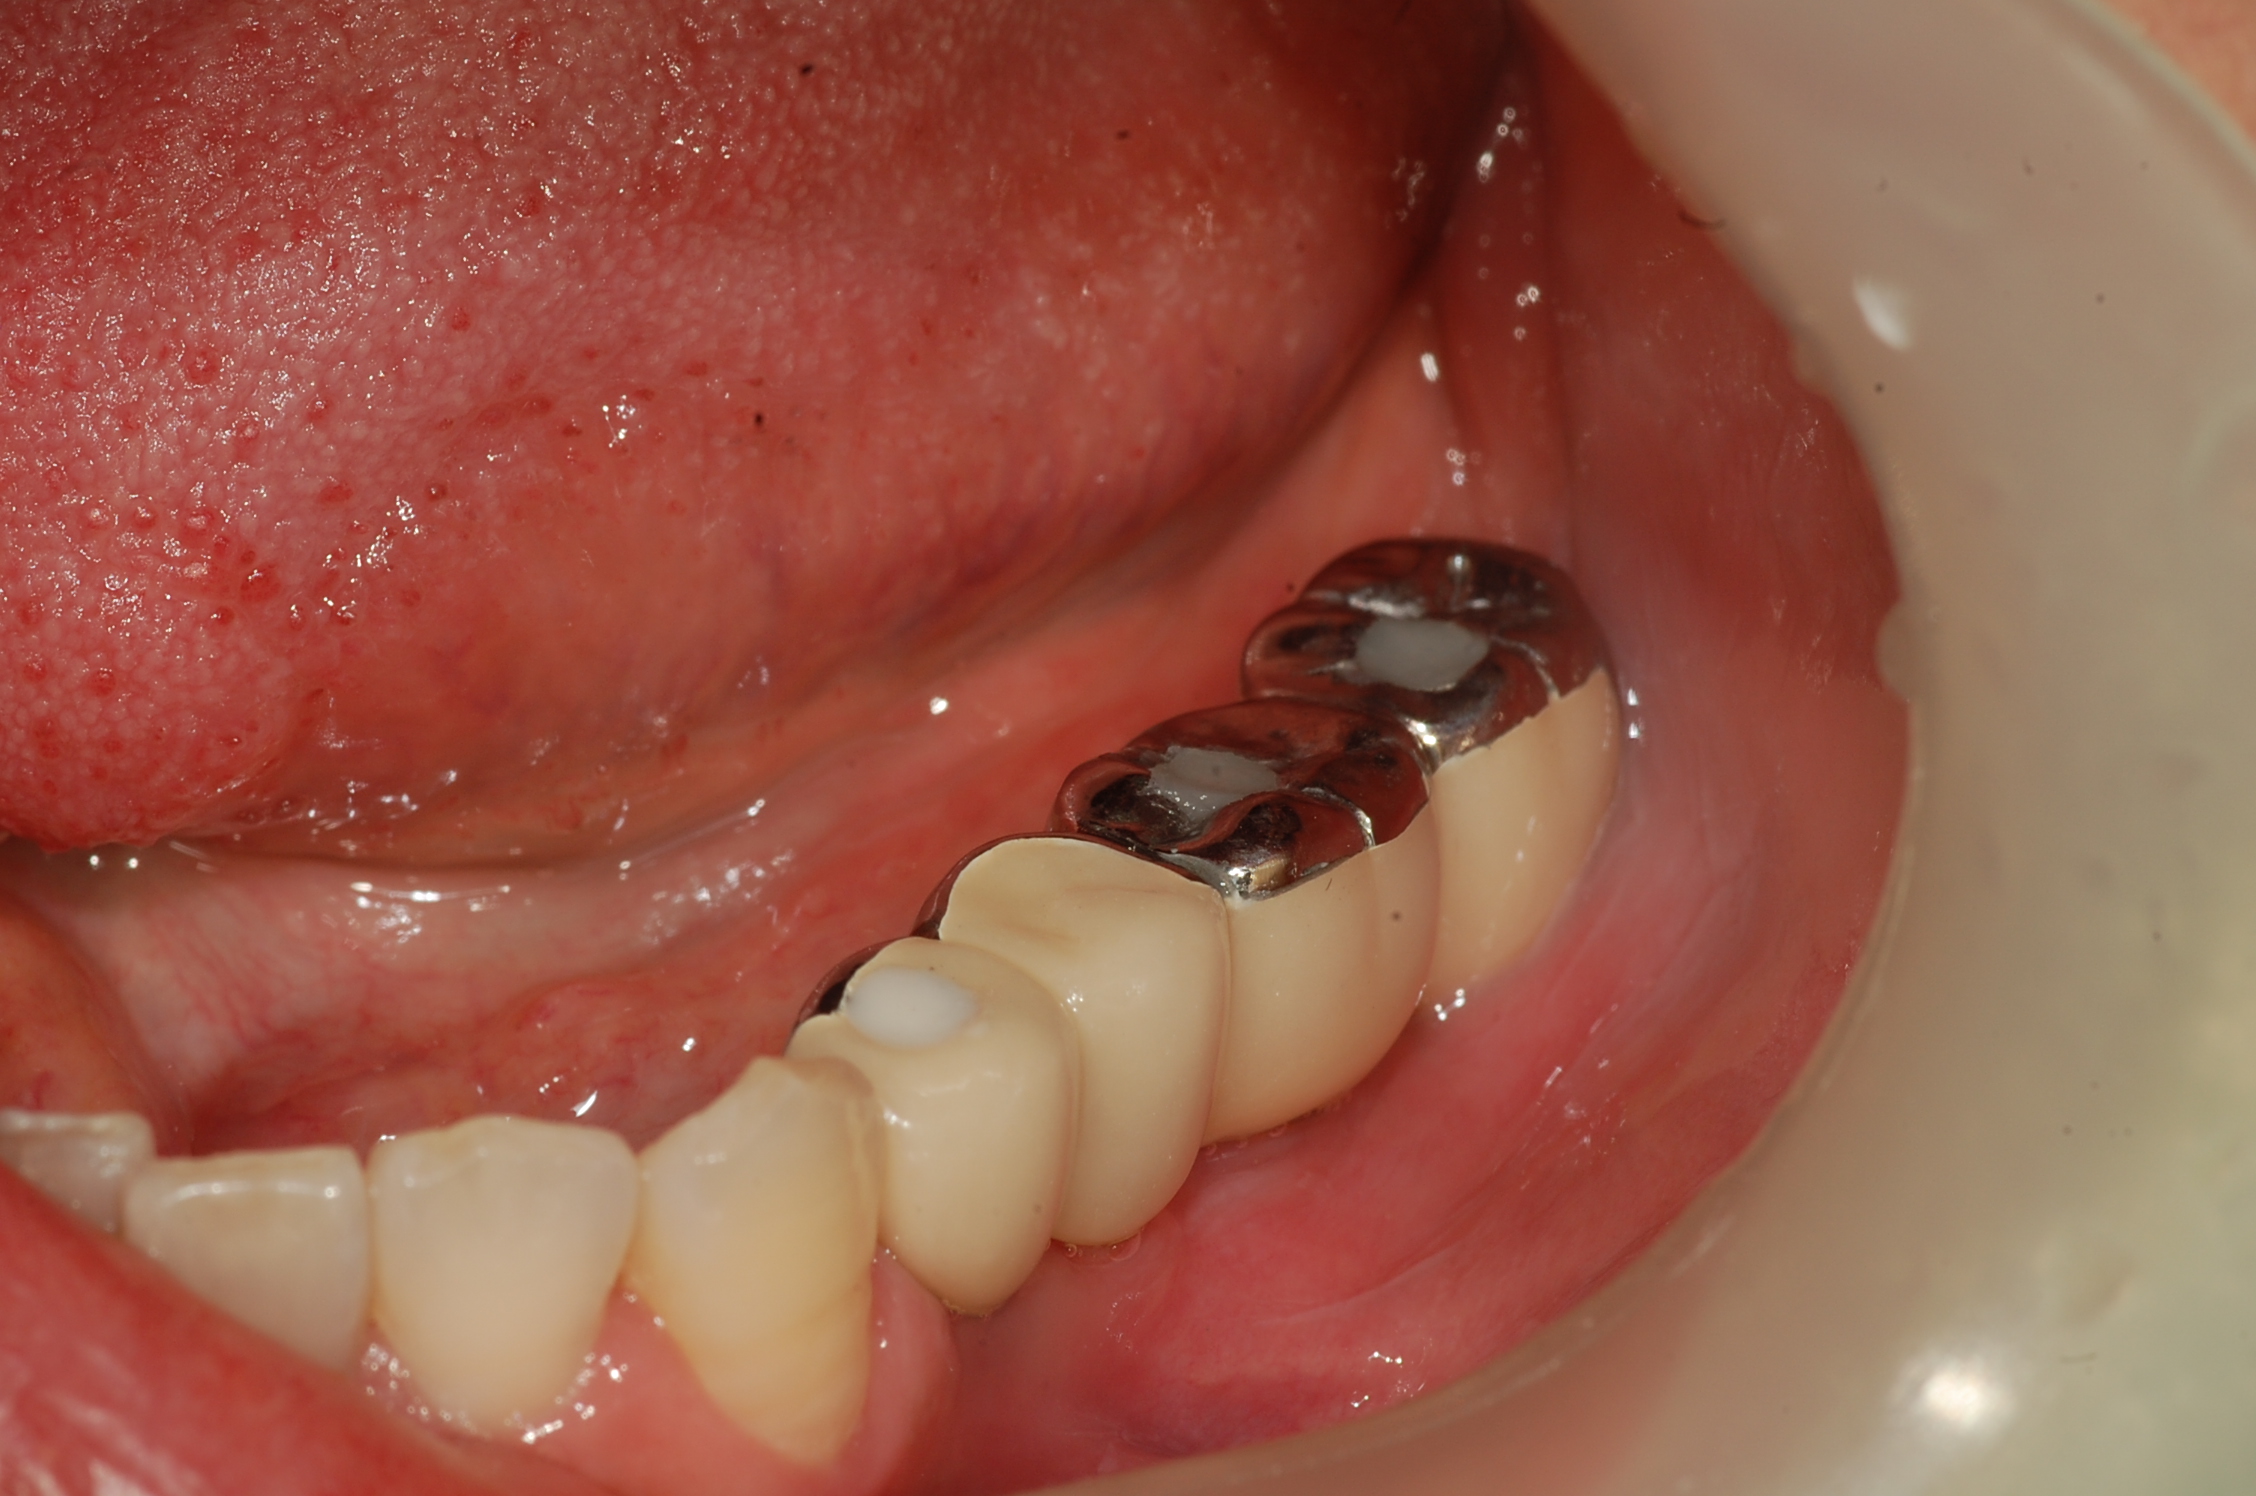

[임플란트] 제목 : 하악구치

임플란트 보철